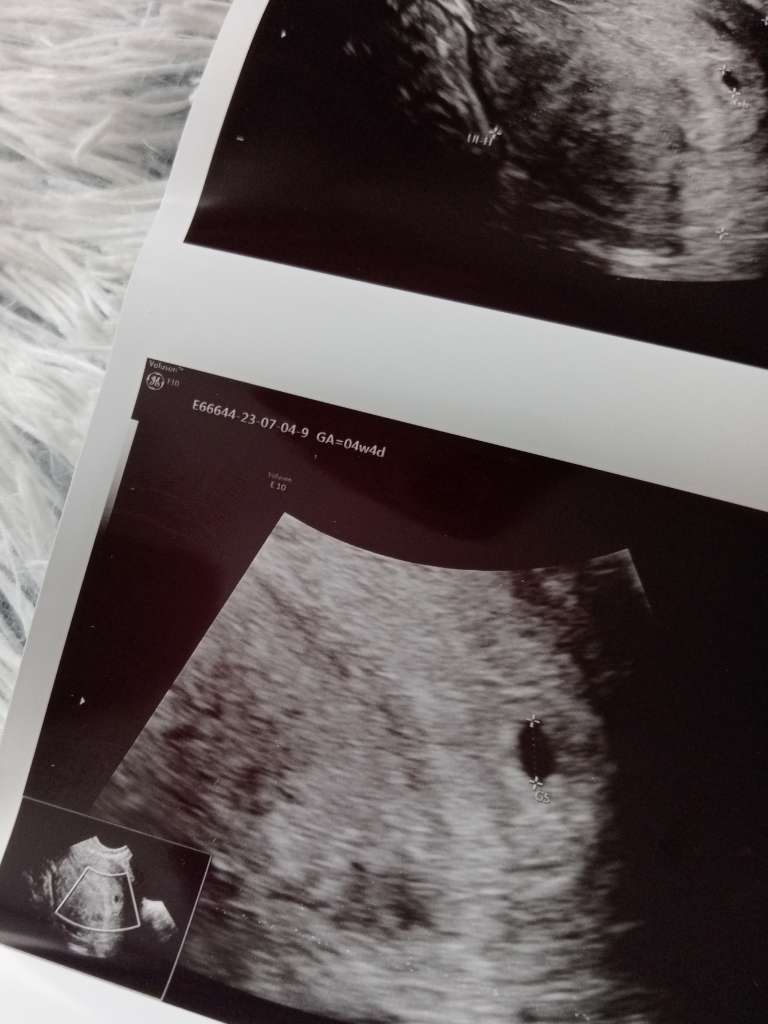

Jaki był u Ciebie dzisiaj tydzień? Widzę ze termin porodu masz dzień wcześniej. Ja idę 11.07 na wizytę, będzie 5+4 i zastanawiam się czy będzie cokolwiek widać, u Ciebie szybko lekarz znalazł pęcherzyk☺️ Gratulacje kochana dobrych wieści i oby samych takich przez 9 miesięcy😍

dziś u mnie 4+4 😊

Załączniki

• c93cfd72-327b-4eed-a497-b1897a7b4be9.jpeg